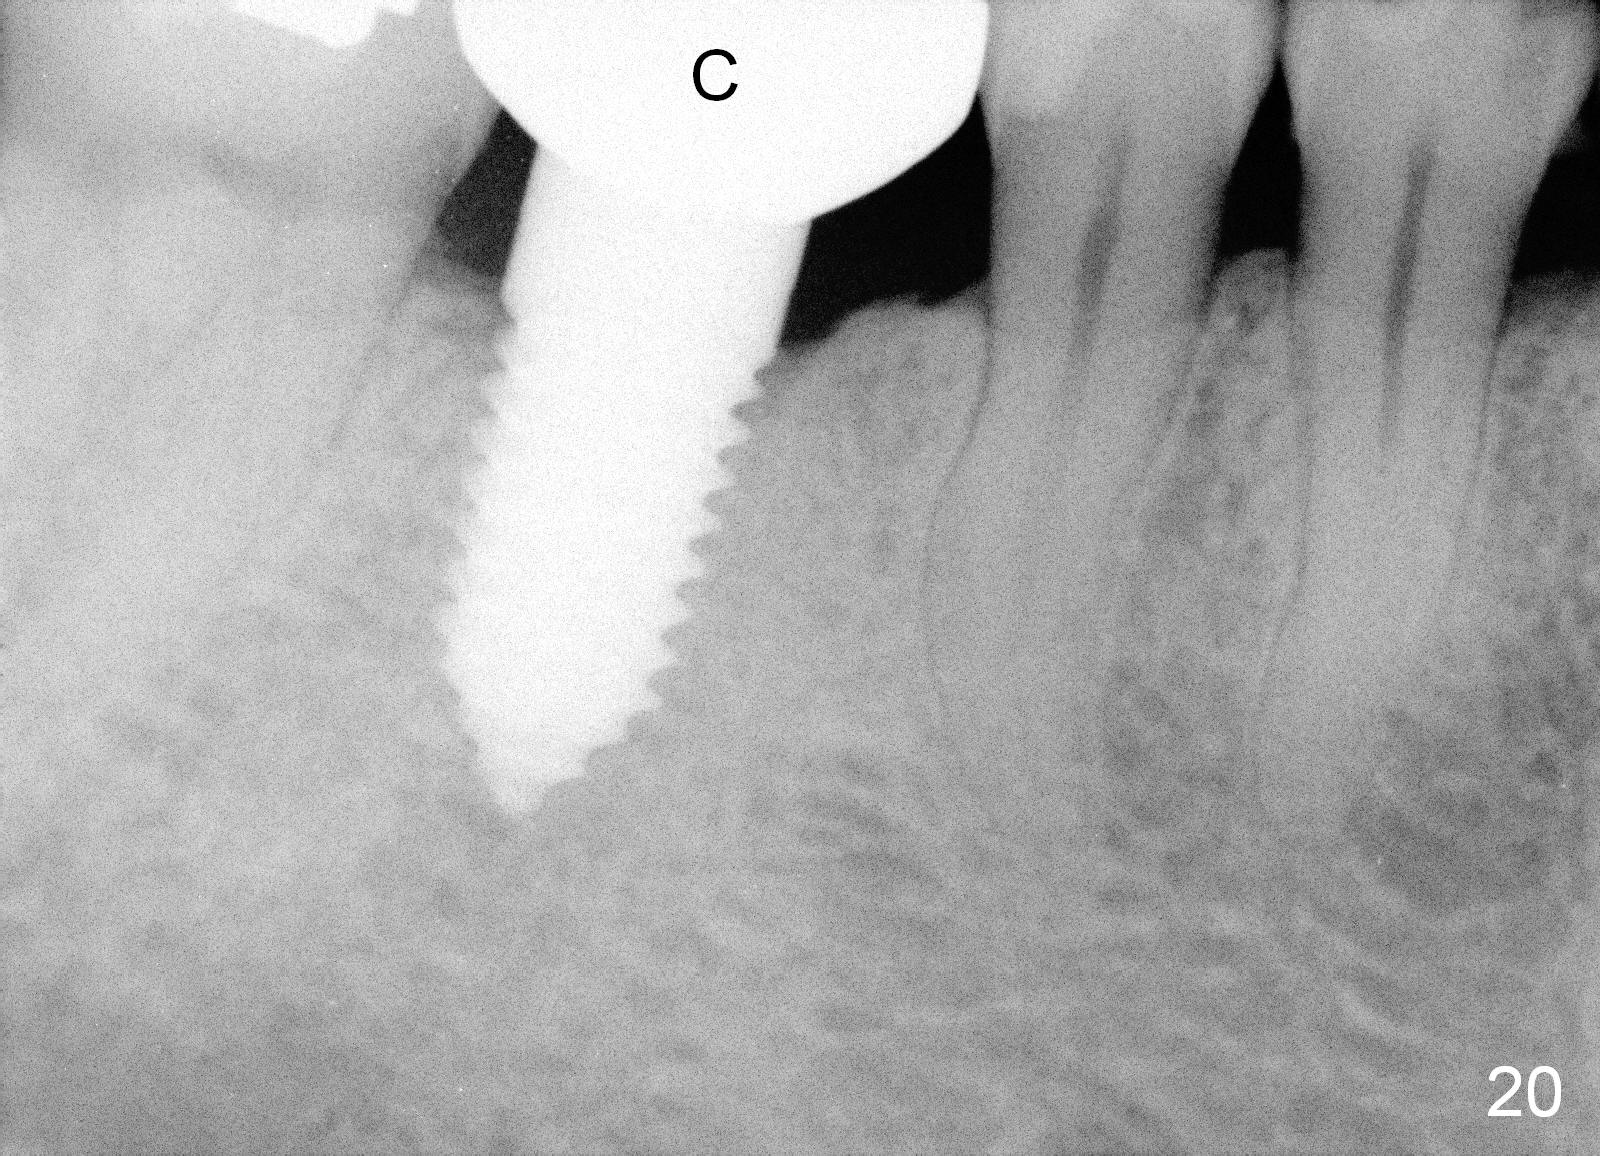

A 38-year-old lady agrees to have implant placement 7 years after loss of the crown of the lower right first molar (Fig.1,2). When the tooth is extracted, the septum is found to be low (Fig.3,4). To confirm it, a PA is taken (Fig.5). To initiate an osteotomy in the septum, it is trans-sectioned with thin osteotomes as shown in Fig.4 insert (black line). A 2 mm pilot drill is placed in the septum (Fig.6: P). The osteotomy is enlarged by 2.5-4.0 mm reamers (Fig.7,8), followed by insertion of 6x17 mm tapered tap at the depth 14 mm (Fig.9). The osteotomy is further enlarged by 4.5 and 5.0 mm reamers. A 6.0x14 mm one piece implant is placed initially. The trajectory is not ideal. A 6.0x14 mm one piece implant is placed initially. The trajectory is not ideal. The implant is removed from the osteotomy partially and reinserted with improved trajectory (Fig.11, compare to Fig.10 (red line)). Primary stability is high. There is not much bone mesiodistally so that the trajectory is easily changed in that direction. After abutment preparation, mixture of autogenous bone (harvested from reamers) and allograft is placed in the residual mesial and distal sockets (Fig.12). To contain the bone graft, an immediate provisional is placed (Fig.13 P). The occlusal plane of the provisional is significantly lower than that of the adjacent teeth to avoid micromovement of the implant. The patient is advised to eat soft food on the left side. Six days postop, the patient returns for prophy. The provisional is removed; the bone graft appears to be incorporating into the socket (Fig.14). After recementation, the provisional remains in place for 3.5 months; PA shows increased bone density in the mesial and distal sockets (Fig.15, compare to Fig.5,11). Due to insurance coverage, the patient defers fabrication of definitive restoration for at least 7 months. The immediate provisional is finally lost 8.5 months postop: the gingiva attaches to the 1-piece implant (Fig.16), while the density of the mesial socket increases (Fig.17 *) with formation of the cortex (lamina dura) coronally (v). Before the provisional (Fig.18 P) is removed for cementation of the definitive restoration, black shadow (*) is noted over the buccal gingiva. It is partially due to buccal placement (Fig.19) and partially due to buccal atrophy over a period of 10.5 months postop. How to prevent buccal placement? Positioning the first pilot drill in the septum buccolingually is a key. Eleven months post crown (Fig.20 C) cementation, the black shadow remains, but there is no tenderness. If the implant threads are immediately underneath the periosteum, there is tenderness.